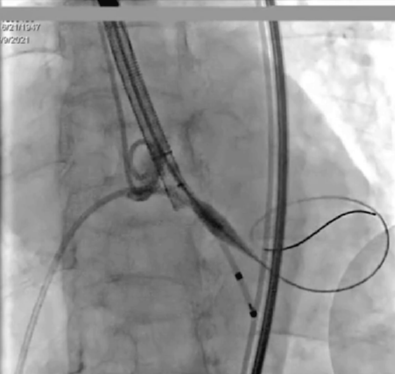

选取20mm球囊180bpm频率下快速起搏预扩。球囊扩张后未见反流,左右冠血流未受影响,选择VenusA-Plus 26型号瓣膜植入。

预扩

输送系统输送至窦底,行主动脉根部造影,借助无冠窦猪尾造影定位,由于该患者基础心率较缓慢,瓣膜无起搏顺利释放。

释放